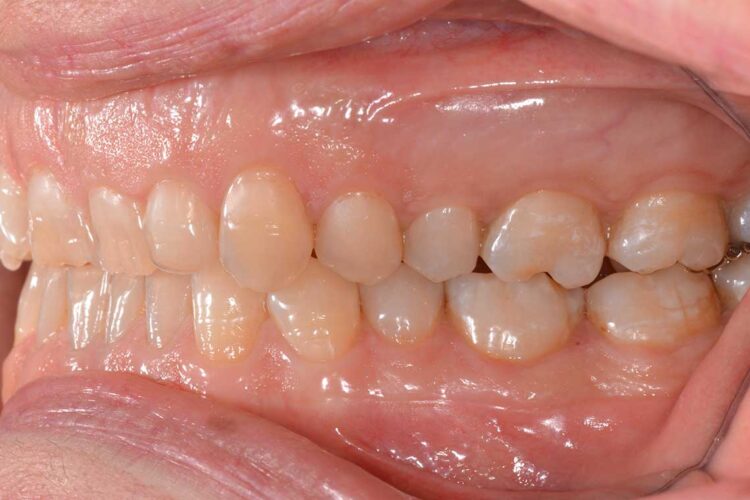

Ortodonzia allineatori – caso clinico 2